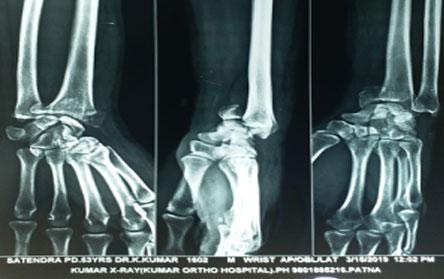

Trauma surgery:

Trauma surgery is a surgical specialty that utilizes both operative and non-operative management to treat traumatic injuries.

The Center of Orthopedics KUMAR ORTHO HOSPITAL ,Patna, offers the entire spectrum of modern orthopedic management, which is effective, patient - friendly & result oriented. In a nutshell, it is one stop treatment for all orthopedic ailments and fractures with emphasis on avoidance of complications, rapid mobilization, decreased period of confinement and an early return to normalcy.